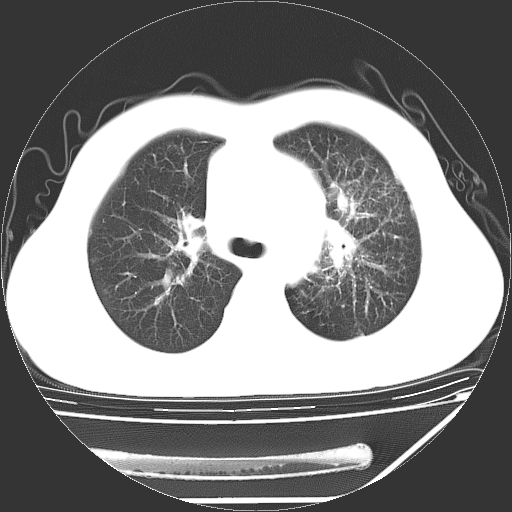

男,13岁,咳嗽、咳痰伴发热一周。

上纵隔课件多枚淋巴结,部分相互融合,左侧支气管壁增厚,肺纹理较右侧增粗,患者,男,13岁,

中上纵隔见多枚淋巴结肿大,部分相互融合成团片,左肺门增大,上叶支气管变窄,肺内多处斑片状 索条状及棉絮状致密影。临床“男,13岁,咳嗽、咳痰伴发热一周。”首先考虑:原发综合征!不除外淋巴瘤可能!

纵隔多发肿大淋巴结,部份有融合改变。双肺血管气管束增厚,以肺门为中心向外周散发,以左肺下叶为明显。考虑淋巴瘤可能性大。不除外原发综合征。

中上纵隔见多枚淋巴结肿大,部分相互融合成团片,左肺门增大,上叶支气管变窄,左肺支气管血管束增粗,可见磨玻璃样影。临床“男,13岁,咳嗽、咳痰伴发热一周。”首先考虑:淋巴瘤可能性大!